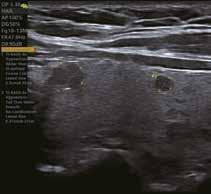

VAid Thyroid bietet einen nicht-invasiven Ansatz zur Erkennung und Beurteilung von Schilddrüsenknoten. Es erkennt automatisch einzelne oder mehrere Läsionen beim Scannen in Echtzeit und zeigt die Größe, die Randmerkmale und die Tl-RADSKlassifizierung der Läsion an.

Unnötige Eingriffe zur Erkennung und Beurteilung von Schilddrüsenknoten werden vermieden.

Intelligente Erfassung und Stadieneinteilung von Schilddrüsenerkrankungen

Schilddrüsenknoten werden in Echtzeit oder auf gespeicherten Bildern erkannt, zusammen mit dem T-RADS-Kategorisierungs- und Berichtstool, wodurch die klinische Routine der Schilddrüsenultraschalluntersuchung genauer und aussagekräftiger wird.